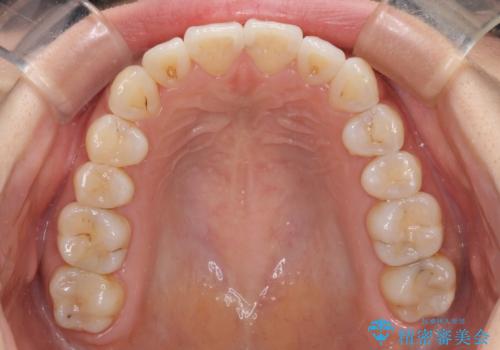

前歯のデコボコが気になる インビザラインによる矯正治療

- 上下前歯のデコボコを気にして来院された患者様です。

インビザラインによる上下歯列の拡大と、IPR(歯と歯の間を削る)にるスペースの獲得により、前歯のデコボコを改善することとしました。

しっかりと装着時間を遵守してくださったので、思い通りの歯列に整えることができました。

結婚式前に終了させることができ、患者様には大変満足していただきました。